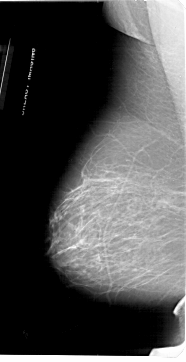

A_1953_1.LEFT_CC

LEFT_CC LINES 6871 PIXELS_PER_LINE 3361 BITS_PER_PIXEL 12 RESOLUTION 43.5 NON_OVERLAY